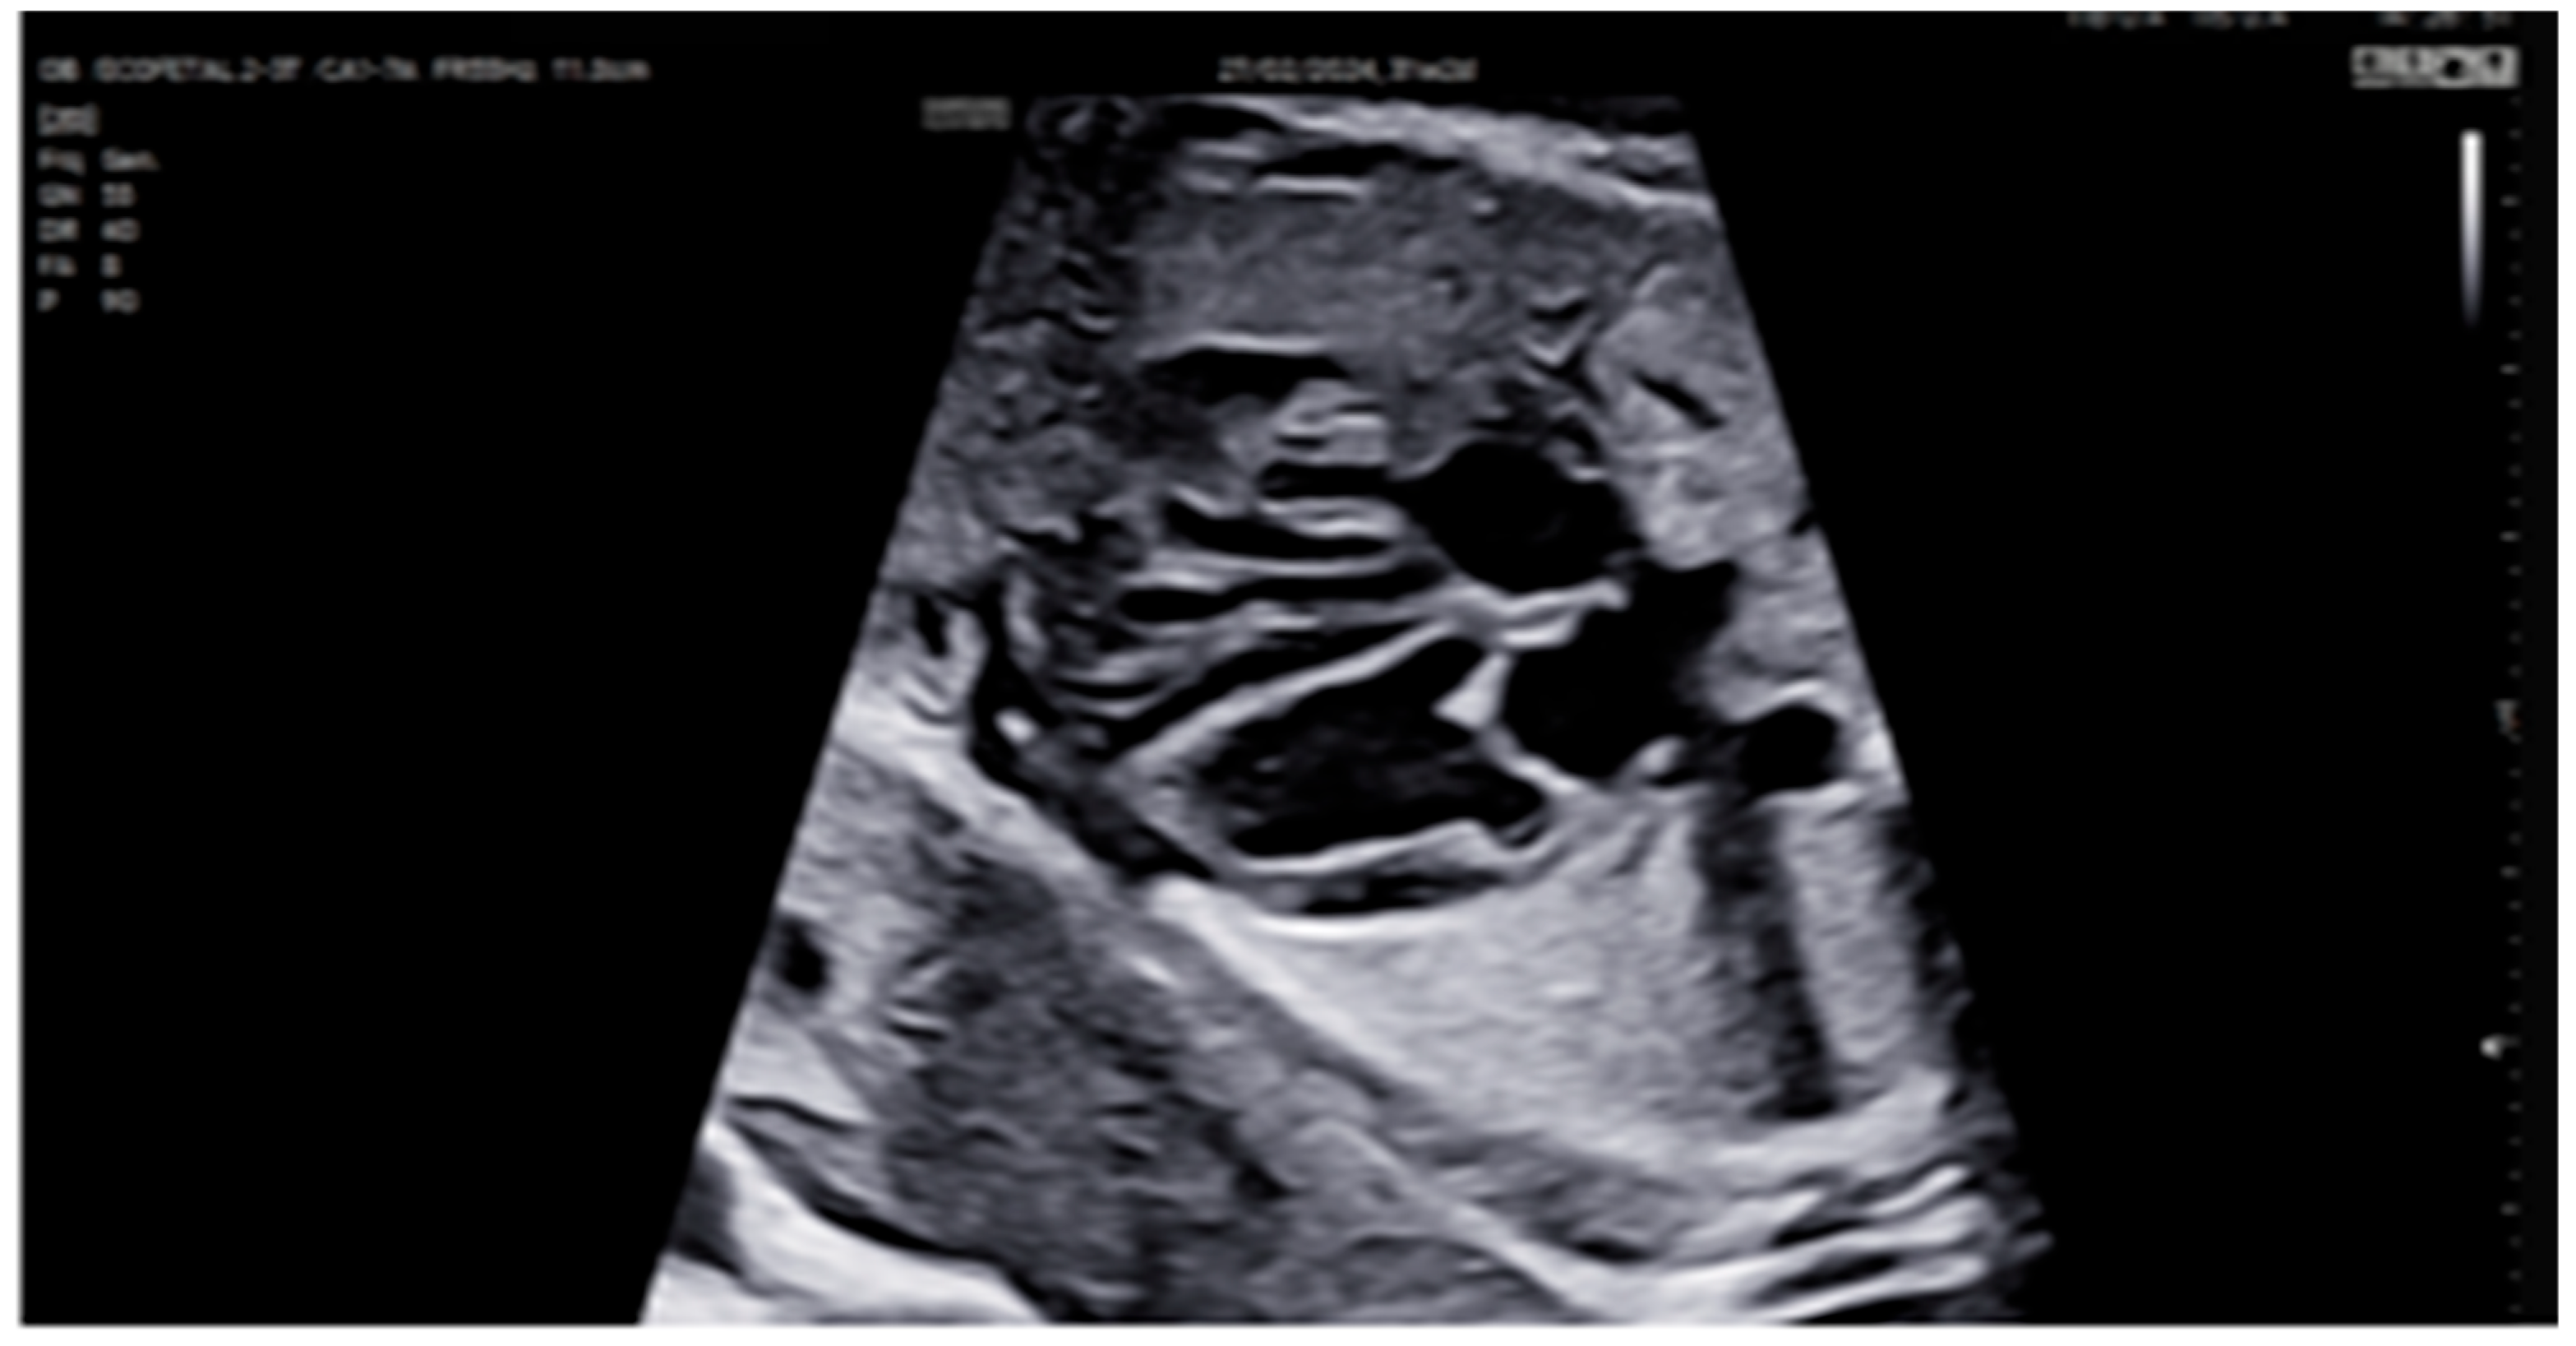

| 31 + 2 | Post-IVIG peak response | 70 | SF: 59% (LV), 52% (RV); marked biventricular improvement | Aortic isthmus 3 mm (Z-score –1.65) |